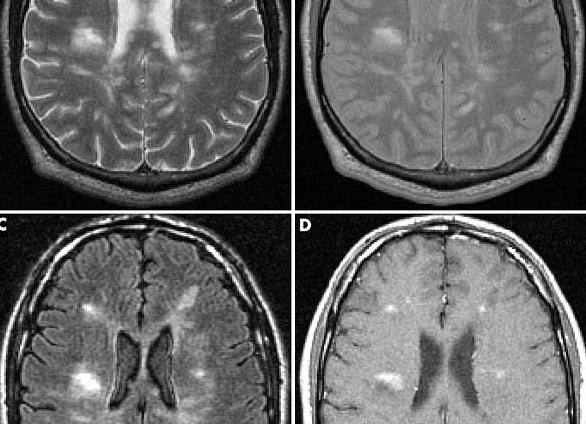

Для больных рассеянным склерозом в качестве метода диагностики используют МРТ спинного и головного мозга. При исследовании в режиме Т2 выявляется большое количество рассеянных бляшек демиелинизации, особенно около желудочков мозга.

Чтобы обнаружить недавно образованную бляшку, следует применять контрастное вещество. Диагноз РС выставляется на основе выявления более 4 демиелинизирующих участков, размером свыше 3 мм, или 3 очагов, находящихся вблизи тел боковых желудочков, в стволе мозга, мозжечке или спинном мозге.

Видимыми признаками рассеянного склероза на МРТ томографе являются множественные очаги демиелинизации (бляшки). Изображения, выполненные в режимах сканирования Т1 и Т2 содержат визуальную информацию о локализации и характерной форме очагов с повышенной интенсивностью сигнала.

- Режим Т1 с гипоинтенсивным сигналом подтверждает наличие аксональной дегенерации (аксонопатии, при которой в нейроне нарушается метаболический процесс), отображенной при рассеянном склерозе на картине МРТ в виде затемненных областей — «черных дыр»

Как правило, изображения получают в режимах Т1 и Т2. Такая картина вмещает наиболее информативное представление о ситуации. На ней можно увидеть бляшки, которые представляют наибольшую опасность. Их интенсивность сигнала более ярко выражена. Каждый процесс сканирования отвечает за определенную функцию:

- Т1 позволяет увидеть сбой в функционировании нейронов, отображая происходящее в виде темных областей на мозге.

- Т2 позволяет просмотреть очаги более четко, оценить сложность поражения мозга болезнью. Данный режим имеет высшую степень интенсивности и используется наиболее часто.

Томографы, основанные на ядерно-магнитном резонансе, имеют два режима работы — Т1 (низкоинтенсивный), на котором распределение жидкости отображается в виде темных пятен, и Т2 (высокоинтенсивный), где жидкость, наоборот, визуализируется ярко.

Признаки рассеянного склероза на МРТ хорошо видны специалисту. Для получения ясной картины на томографе делают снимок головного и спинного мозга в трех проекциях. Сами миелиновые оболочки нервов имеют вид своеобразных «муфточек», но видны они только под микроскопом. Однако на снимках МРТ при рассеянном склерозе видны бляшки в виде темных (на Т1-снимках) и светлых (на Т2-снимках) пятен. К тому же при достаточно обширном воспалении наблюдаются отеки, которые имеют свойство сливаться друг с другом, достигая в диаметре нескольких сантиметров.

В заключение МРТ вносятся данные о структурах мозга, в которых наиболее вероятно появление бляшек, а также полное описание зафиксированных во время обследования патологических структур. Чаще всего патология проявляется в области мозолистого тела и мозговых желудочков.

Бляшки различны по размеру (более мелкие свидетельствуют о том, что заболевание началось недавно), по форме (более круглая означает острый склероз, овальная — хронический). Когда применяются контрастные препараты, медик смотрит на интенсивность изменения цвета — она может сказать о том, рецидивирует ли заболевание (в случае неравномерного окрашивания). Таким образом, рассеянный склероз на МРТ можно диагностировать с довольно высокой точностью.

МРТ признаки рассеянного склероза. Множественные очаги, прилежащие к желудочкам мозга (красная стрелка); очаги продолговатой (овоидной) формы, ориентированные поперек длинной оси желудочков мозга (желтая стрелка); множественные очаги в мозговом стволе и мозжечке (справа). Подобные поражения часто именуют «пальцами Доусона», они отражают демиелинизацию белого вещества головного мозга вдоль малых мозговых вен, располагающихся перпендикулярно мозговым желудочкам.

Пальцы Доусона. Считается, что «пальцы Доусона» — характерный симптом рассеянного склероза — возникают в результате воспаления тканей, окружающих пенетрирующие венулы, которые располагаются перпендикулярно по отношению к длинной оси боковых желудочков.

На представленных МР-томограммах типичными для РС являются следующие изменения:

- Очаги продолговатой формы, ориентированные перпендикулярно желудочкам мозга (пальцы Доусона)

- Усиление сигнала от данных очагов после введения контраста

- Множественность поражений и их расположение вблизи желудочков

На МР-томограммах (исследование сделано через три месяца после клинического дебюта) определяются типичные признаки рассеянного склероза:

- Множественные очаги, накапливающие контраст

- Большая часть этих очагов вплотную прилежит к коре: они должны быть расположены в области дугообразных волокон

- Все эти очаги являются недавно возникшими, поскольку контрастное усиление очагов при введении препаратов гадолиния наблюдается только в течение месяца (диссеминация во времени).